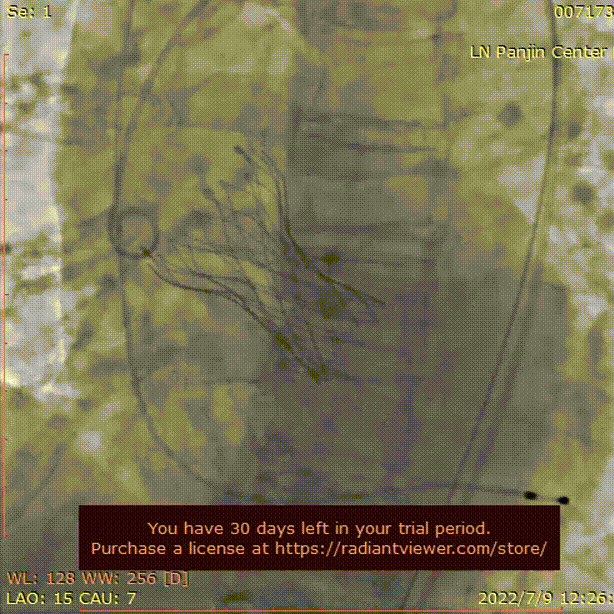

主动脉根部测量

CT特点:Type0型二叶式主动脉瓣,左右冠不同窦;冠脉开口高度可,无冗长瓣叶;横位心,心室壁肥厚。

瓣上测量

瓣上测量:瓣叶重度钙化伴增生肥厚,钙化分布不均,主要分布于瓣叶边缘及后壁交界附着缘。